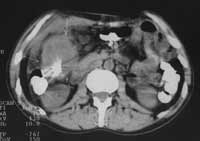

В 10-ти случаях выявлены признаки характерные для рака ободочной кишки: неравномерное утолщение стенок ободочной кишки от 1,0 до 2,6см, нечеткость контуров, повышение плотности окружающей клетчатки, уплотнение переднего листка околопочечной фасции (в случаях рака восходящей и нисходящей кишок) (Рис. 1- 4). В 2-х случаях рак ободочной кишки сопровождался  признаками кишечной непроходимости (Рис. 5). В одном случае массивная опухоль исходила из правой почки и вовлекала восходящую кишку. В другом — выявлена опухоль имеющая неоднородную мягкотканную плотность, относительно четкие контуры расположенная, премущественно экстраорганно по отношению к нисходящей кишке (Рис. 6). В одном случае при пероральном контрастировании ободочной кишки создалось впечатление ракового поражения селезеночного угла толстой кишки, для уточнения исследование повторили после очистительной клизмы и раздувания — в результате выявлен полип на ножке (Рис. 7). При обследовании постоперационных больных — в 1-м случае выявлен околоободочный абсцесс, в другом — явления анастомозита после левосторонней гемиколонэктомии, проявляющегося утолщением стенок кишки в зоне анастомоза до 6мм с выраженным расширением проксимальной части кишки. В двух случаях при КТ исследовании не получено убедительных данных за опухолевое поражение ободочной кишки хотя данные колоноскопии указывали на раковое заболевание или малигнизированный полип.

Рис. 2. Рак слепой кишки: неравномерное утолщение стенок, инфильтрация окружающей клетчатки.